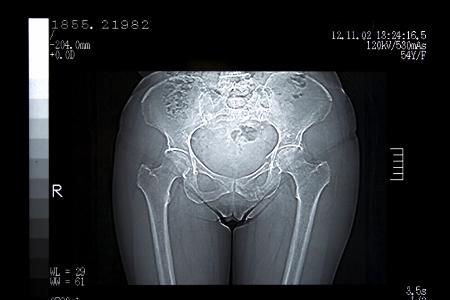

Der Vagina-Report: 50 kuriose Fakten über das weibliche Geschlechtsteil

Während Männer mit ihrem "besten Stück" gerne prahlen, gehen Frauen mit ihrer Vagina viel zurückhaltener um. Keine falsche Bescheidenheit: Wir haben die 50 überraschendsten für Sie gesammelt.